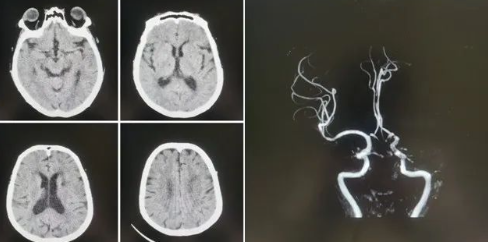

品質(zhì)國文丨國文醫(yī)院神經(jīng)介入科成功實施高難度機械取栓術(shù)

近日,國文醫(yī)院神經(jīng)介入科團(tuán)隊成功實施了一例高難度的腦血栓機械取栓術(shù),為一名急性腦梗死患者打通了“生命通道”。這一手術(shù)的成功,不僅標(biāo)志著國文醫(yī)院在急性缺血性腦卒中救治領(lǐng)域的技術(shù)水平邁上了新臺階,也為區(qū)域卒中中心建設(shè)增添了新的里程碑。 閱讀量:2141